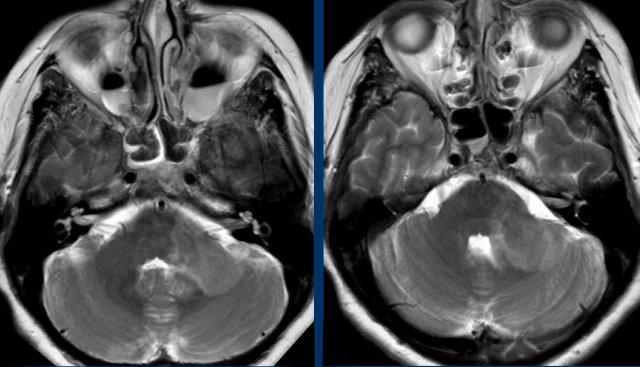

Những hình ảnh này của một phụ nữ 58 tuổi với các triệu chứng thần kinh không đặc hiệu kéo dài nhiều năm, được điều trị bởi bác sĩ phục hồi chức năng.

Hình ảnh

FLAIR 3D trục ngang với ức chế mỡ cho thấy nhiều tổn thương tăng tín hiệu T2 dưới lều tiểu não ở hành tủy bên trái và bán cầu tiểu não hai bên.

FLAIR 3D mặt phẳng vành với ức chế mỡ cho thấy các tổn thương chất trắng hợp lưu quanh não thất và dưới lều tiểu não.

Continue with the next images…

MRI cột sống cổ và cột sống ngực cho thấy nhiều tổn thương trong tủy.

Hình ảnh FLAIR 3D mặt phẳng đứng dọc cho thấy nhiều ngón Dawson hợp lưu và hình ảnh FLAIR 3D mặt phẳng trục ngang cho thấy nhiều tổn thương T2 ở thân não.

Conclusion

Radiological consistent with Multiple Sclerosis.